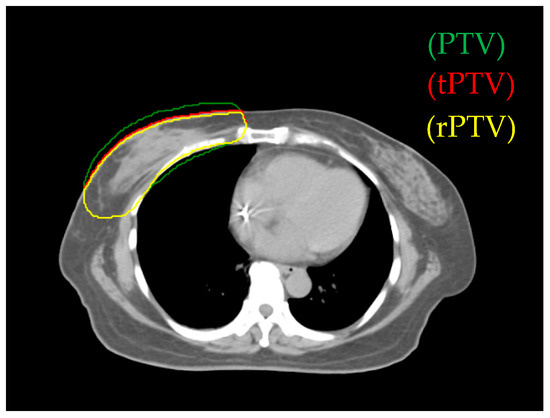

The software used for treatment planning was the Pinnacle3 version 9 RTP. We defined true PTV (tPTV) as the effective PTV margin delineated by the physician after excluding the error region (the part of air and lung). To decrease the surface for achieving greater skin sparing, 0.3 cm retraction of tPTV at the upper border was applied and defined as reduced PTV (rPTV) (see Figure 1). The planning technique extended rPTV to 0.5 cm and added 0.5 cm width in 90% prescription dose constraint circle and 1cm gap as addition area. In all plans, the prescription dose was 50.4 Gy in 28 fractions to the right breast PTV (Table 1). The Elekta Synergy medical linear accelerator was used, the photon energy was 6 MV.

Figure 1.

The green area is the planning target volume (PTV), the red area is the true PTV (tPTV), and yellow area is the reduced PTV (rPTV).